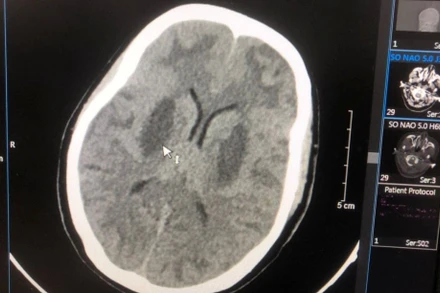

Thời gian qua, Trung tâm Chống độc, Bệnh viện Bạch Mai đã tiếp nhận nhiều trường hợp ngộ độc do sử dụng thuốc lá điện tử. Điển hình là nữ bệnh nhân 20 tuổi ở Hà Nội được đưa vào cấp cứu trong tình trạng hôn mê sâu, suy tim, suy thận, tổn thương não, tổn thương gan.